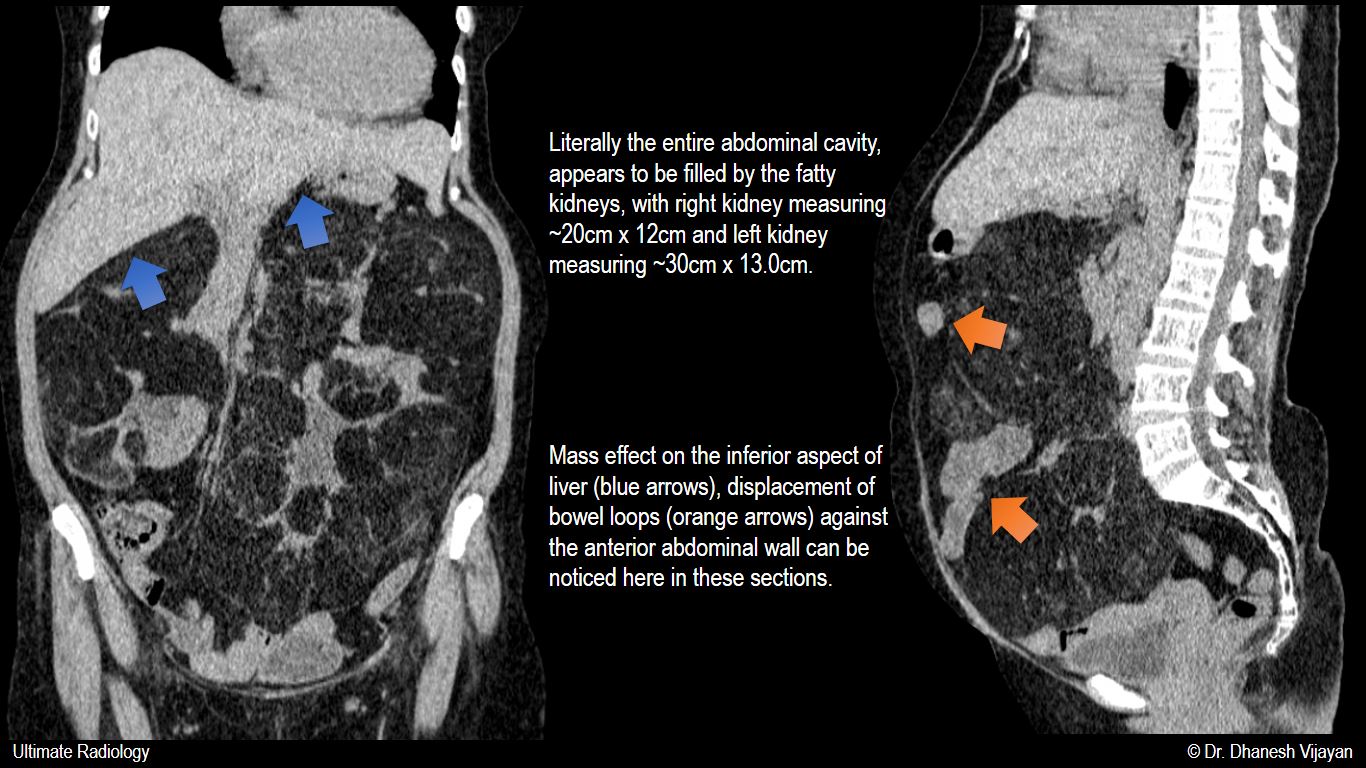

From ultimate-radiology.blogspot.com

Ultimate Radiology RARE Extreme case of bilateral massive renal What Is Enlarged Kidney hydronephrosis can lead to kidney infections, and in some cases, complete kidney function loss or death. Treatment for hydronephrosis depends on what's causing the condition and how severe it is. hydronephrosis occurs when a kidney has an excess of fluid due to a backup of urine, often caused by an. the kidneys are responsible for filtering the. What Is Enlarged Kidney.